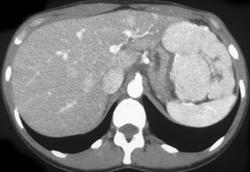

Hepatomas in A Cirrhotic Liver